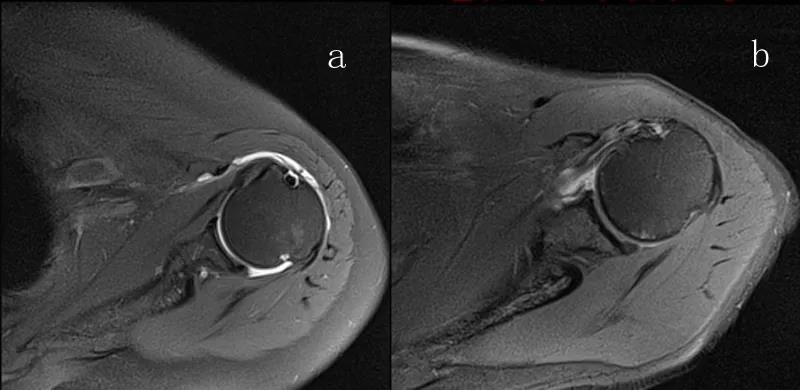

图23 横断位a.正常肩胛下肌;b.肩胛下肌损伤